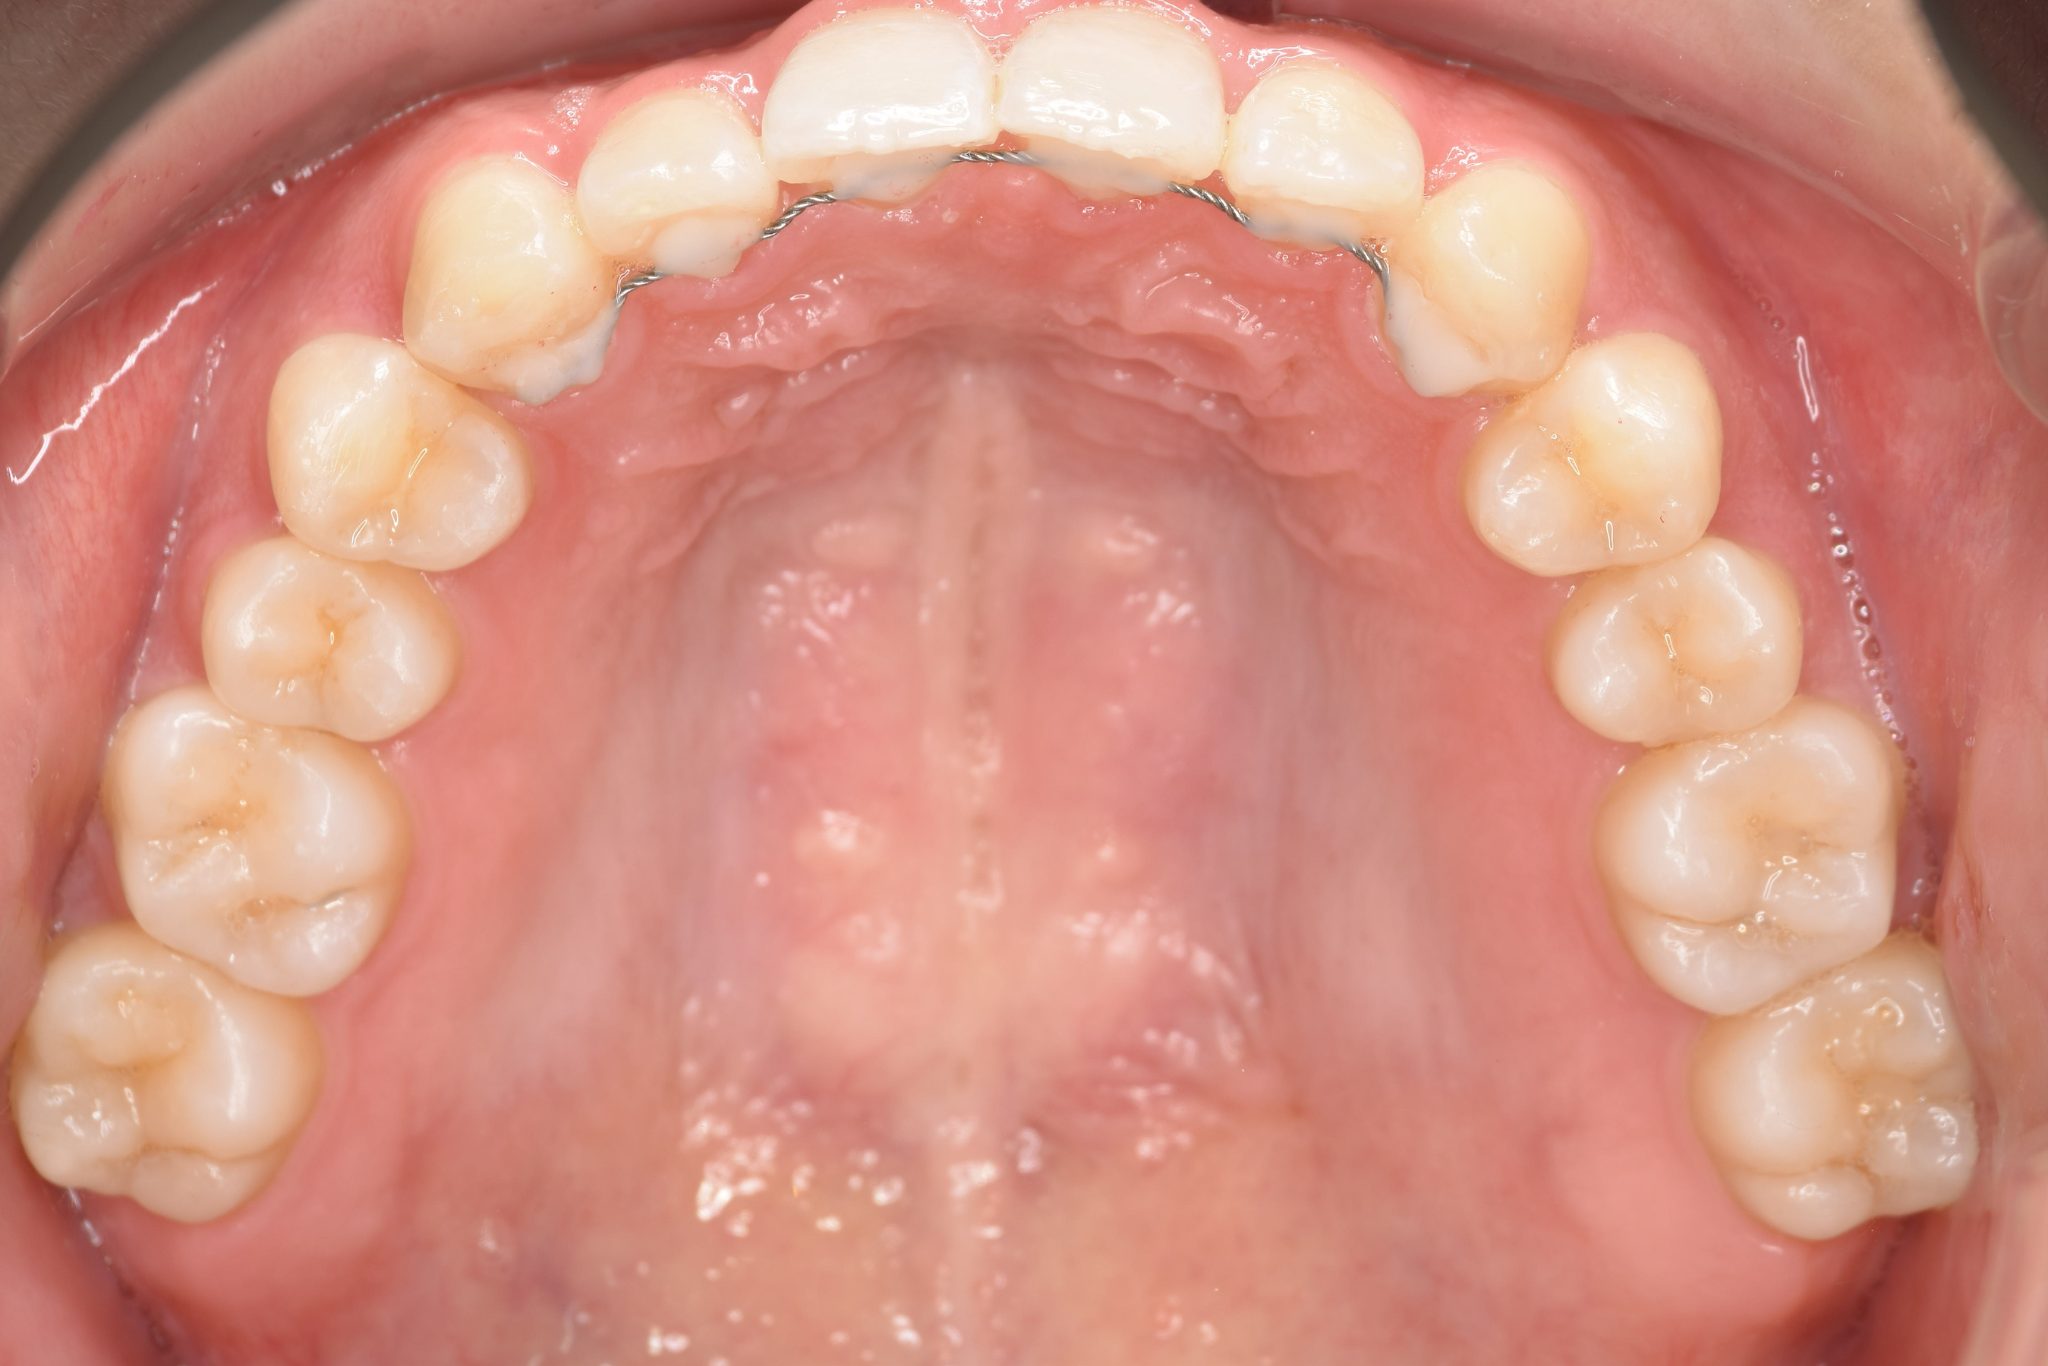

アフター

インビザライン矯正治療|症例_315

主訴 食べ物を前歯で噛み切れない|上顎の右側の歯が重なっている|下の歯がガタガタ

施術内容 MSEと下顎リンガルアーチを用いて上下顎骨を拡大した。

その後アライナー型矯正装置(インビザライン)を用いて非抜歯で歯牙を配列した。

口元の突出感、鼻閉症状、鼾は改善された。